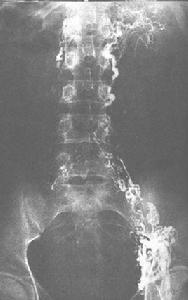

淋巴造影可用來判斷有無淋巴管阻塞以及明確梗阻的部位,對臨床診斷和治療有很大幫助。分析淋巴管造影的結果時,必須注意淋巴管的數量、行徑、輪廓、管徑和瓣膜情況。現把淋巴管阻塞時常見的X線徵象綜合為以下幾種。

淋巴管逆流

表現為淋巴管逆向充盈。如發現盆腔臟器周圍淋巴管逆向充盈,則表示該側骼總淋巴結或腰淋巴乾有阻塞。

淋巴管側支通路的出現是淋巴管阻塞最常見的徵象之一,也是機體用來克服阻塞的主要途徑。淋巴管的側交通路有二種基本形式。

①淋巴、靜脈吻合:在淋巴管梗阻區域,靜脈內見到造影劑。即證明有淋巴靜脈吻合存在。淋巴造影常不能直接看到通路。

②淋巴、淋巴吻合:是最常見的側支通路,類似於血管阻塞後產生的側支循環。如當腰淋巴於完全阻塞時,造影劑通過主動脈分叉處交通淋巴管分流到對側,顯示對側腰淋巴乾。又如阻塞位於腹股溝或髂下區,則在大腿會陰部、外生殖器和前腹壁可顯示廣泛的皮下側支淋巴通路。